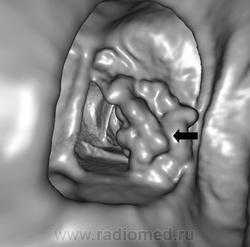

(Слева) Т1-ВИ, сагиттальная проекция: неровность контуров обращенных друг к другу краев остистых отростков L4 и L5 в классическом сочетании с гипертрофией желтой и межостистой связок.

(Справа) Т2-ВИ, сагиттальный срез: классическая картина болезни Бааструпа в виде кистозной дегенерации соприкасающихся поверхностей остистых отростков, определяемой в виде фокусов усиления сигнала. Видны признаки выраженной гипертрофии желтой связки, а также тяжелого дегенеративного поражения дугоотростчатых суставов.